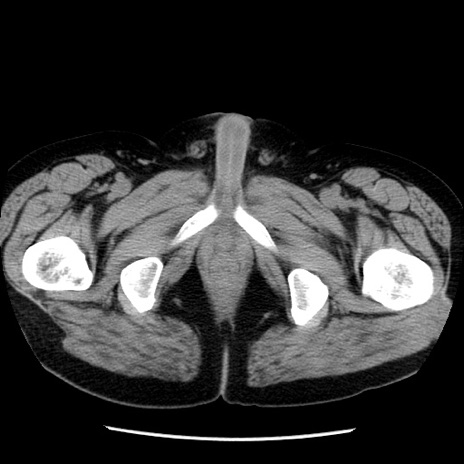

症例29(横断像)

【症例】40歳代男性

【現病歴】2日前から胃痛あり。徐々に周期的な激痛に変化した。本日になっても激痛があるため受診。

【身体所見】意識清明、BT 38-39℃台あり、腹部:膨満、やや硬、右下腹部に圧痛あり。

【データ】WBC 8500、CRP 23.26